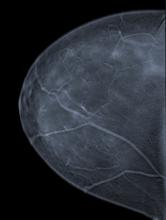

Hologic Inc. is a developer, manufacturer and supplier of diagnostic products, medical imaging systems and surgical products, with an emphasis on serving the healthcare needs of women. It will showcase its portfolio of products for breast cancer screening and diagnosis, breast biopsy, osteoporosis risk assessment and extremity imaging at the annual meeting of the European Society of Radiology, in Vienna, Austria, March 6-10. Hologic is offering three tomosynthesis-related events at ECR.

The majority of certified breast imaging facilities now have full-field digital mammography (FFDM) imaging systems. This is according to the U.S. Food and Drug Administration’s (FDA) data on the Mammography Quality Standards Act’s (MQSA) program and facilities.